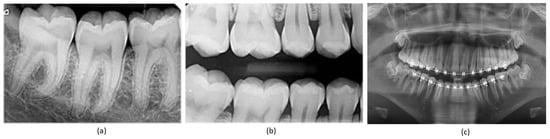

Teeth segmentation is pivotal in the clinical diagnosis of oral diseases, offering essential precision in surgical planning through the accurate delineation of teeth boundaries [,]. In orthodontics, real-time information regarding teeth movement and root depths is crucial for immediate assessment of a patient’s dental alignment and for accelerating the orthodontic treatment cycle []. The prerequisite for achieving this is the precise segmentation of teeth in dental panoramic X-ray images [], which has additional applications in forensic identification [], age estimation, and the analysis of hidden dental structures, including benign or malignant masses []. Dentistry extensively utilizes radiographic images for diagnosis, given their comprehensive visualization of the internal structure of the mouth []. Extra-oral radiographs, encompassing panoramic and cephalometric images, capture the complete dentition and surrounding areas, providing critical insights into a patient’s teeth, as demonstrated in Figure 1. However, manual and semi-automated segmentation approaches for teeth and tissues in these radiographs often prove time consuming, tedious, and subjective, with their efficacy heavily reliant on the dentist’s expertise. Additionally, segmentation in low-quality image settings presents even greater challenges. Given these circumstances, the development of an automatic, accurate, and efficient teeth segmentation method is paramount.

Figure 1.

Types of X-ray images: (a) periapical X-ray; (b) bitewing X-ray; (c) panoramic X-ray.